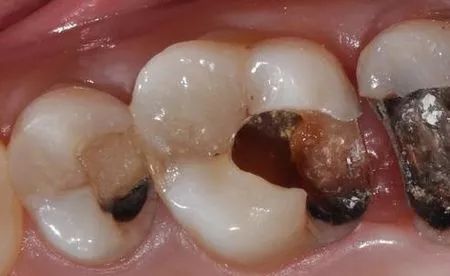

你睇到嘅蛀齒可能唔系全部

運氣唔好嘅話,佢可能系咁樣嘅↓↓

所以眼見唔一定系真實嘅,肉眼睇到針孔大小嘅一個蛀洞,可能牙齒裏面已經被掏空。可能牙齒裡面已經被掏空,無論有幾細嘅蛀洞,都應該立即補上。細細個洞唔補,大個洞啖苦。